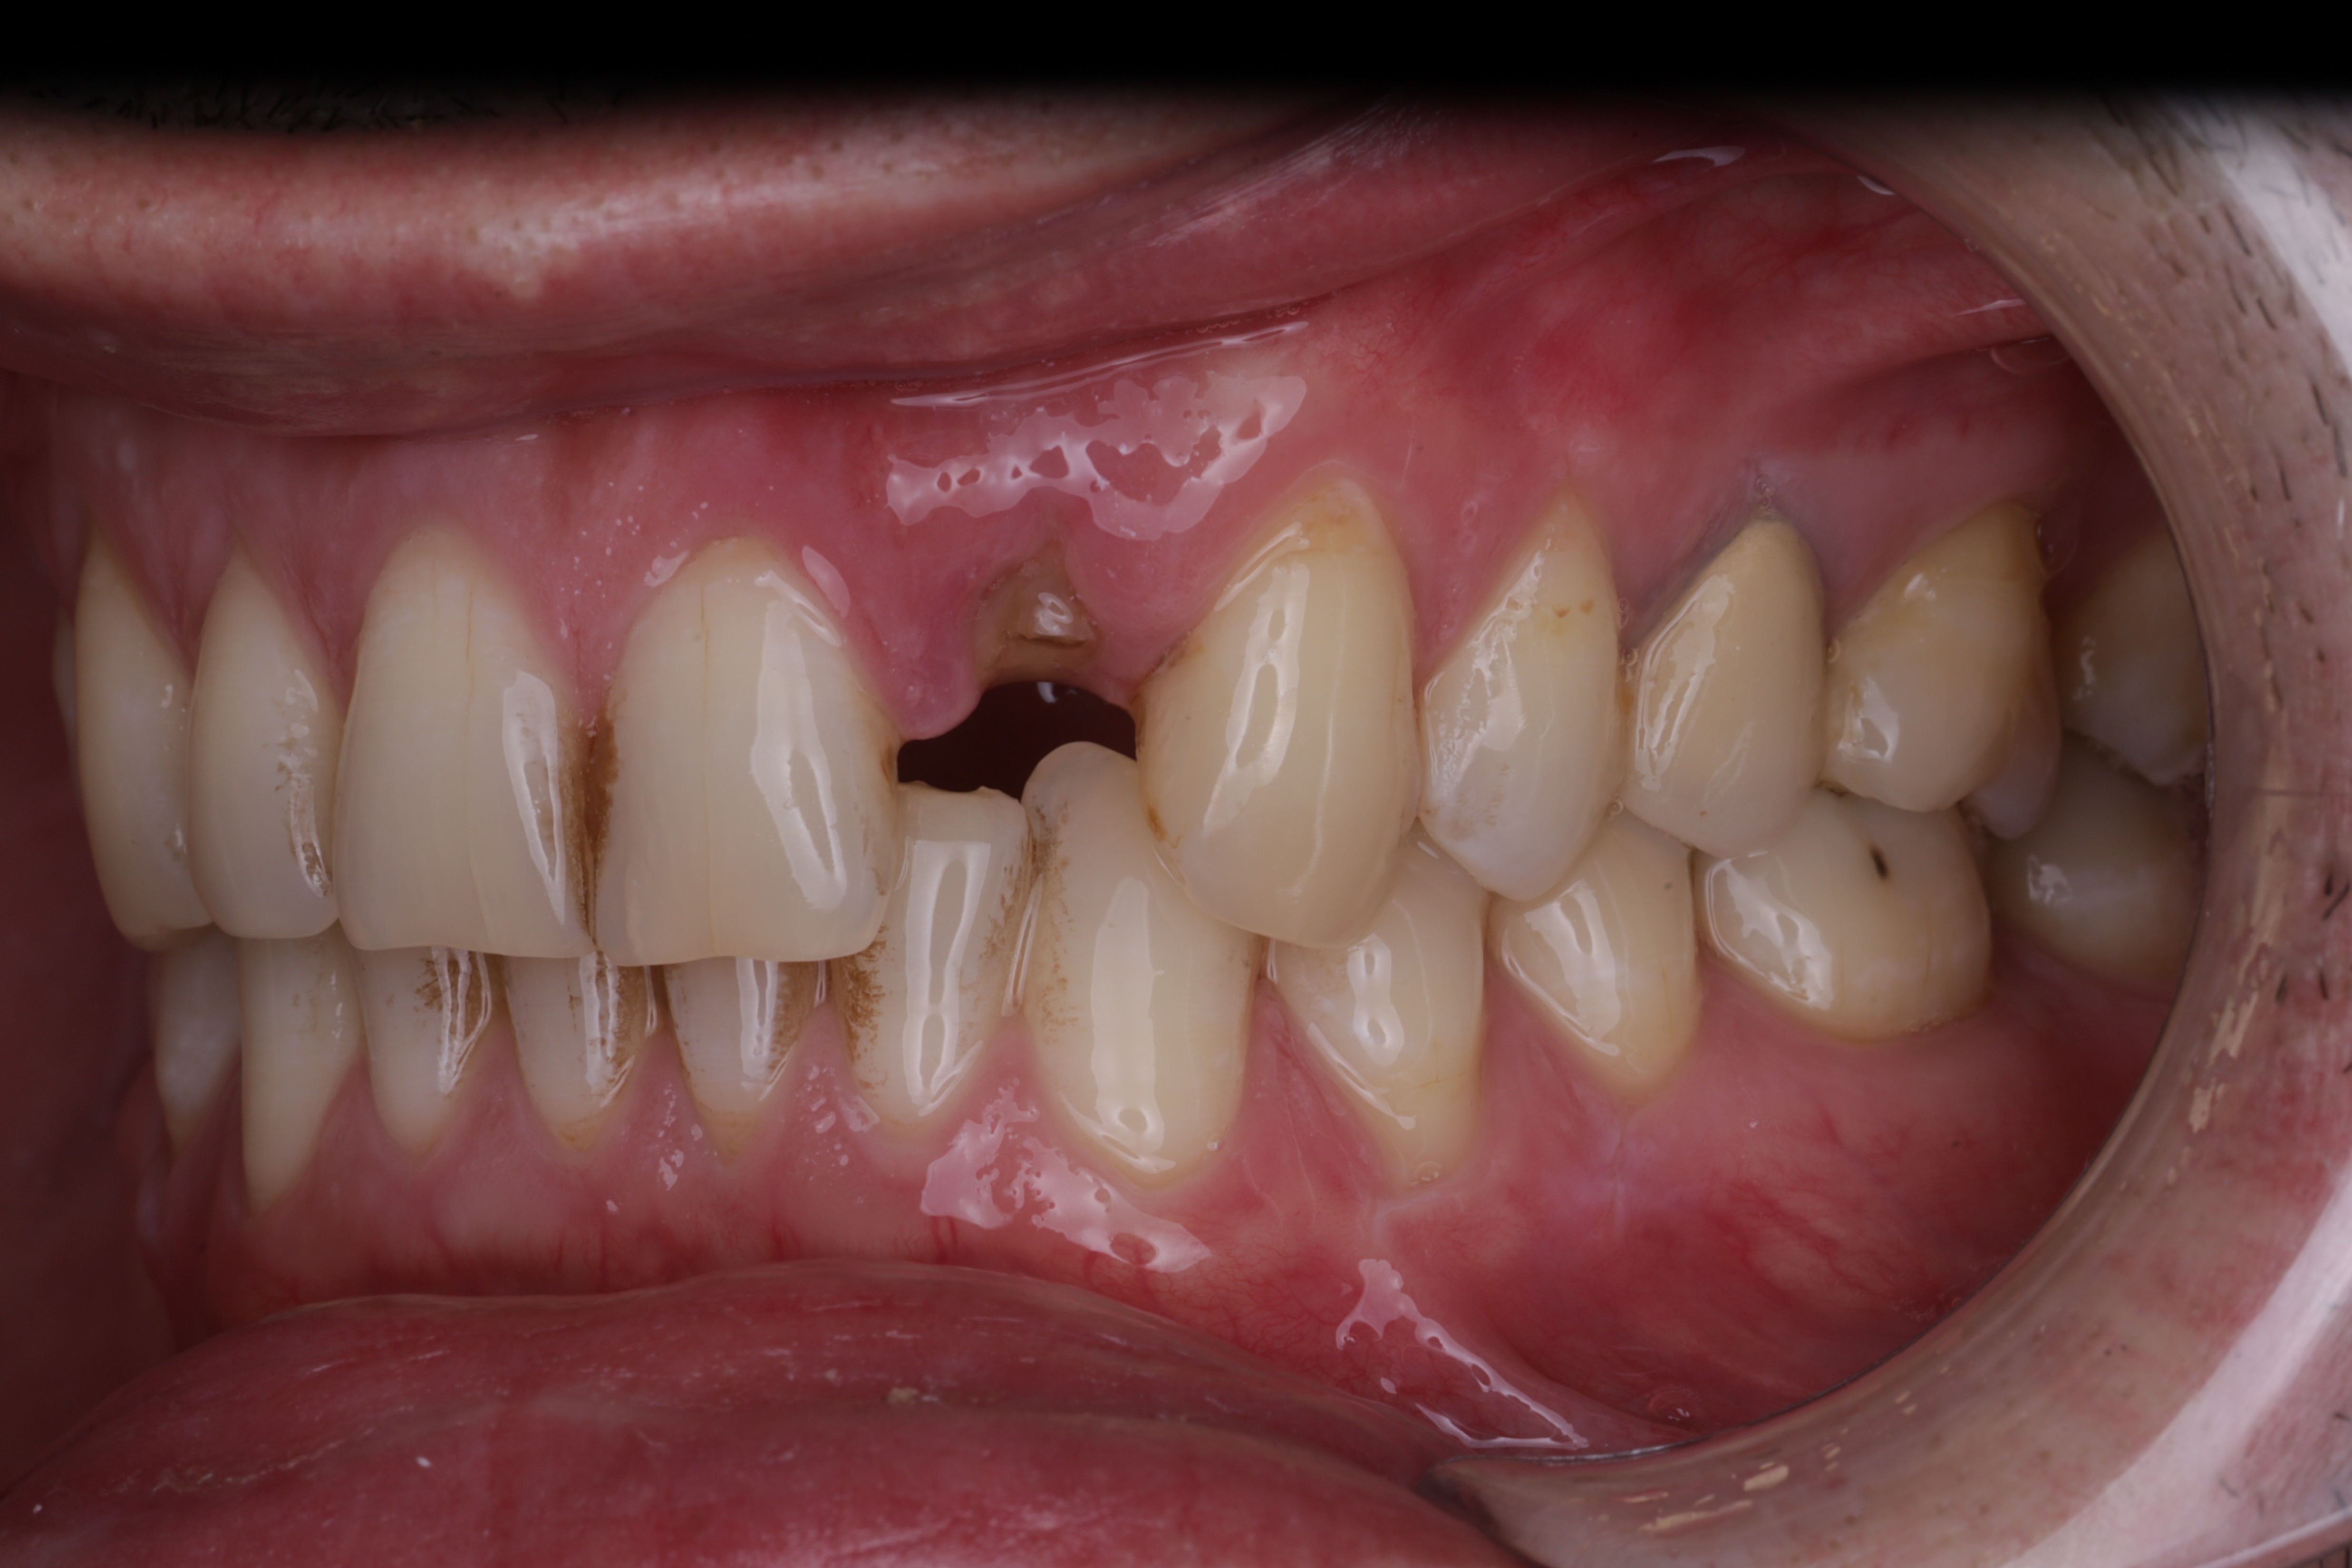

Клиническая картина с которой пациент обратился к нам:

Исходная клиническая ситуация